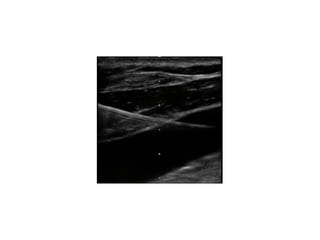

Figure 2: Ultrasound image of the left side of the neck showing normal

anatomy. CA: Carotid artery; IJV: Internal jugular vein

5353 the right sideof the neck carefully using a portable ultrasound (US) machine (IMAGIC Agile, Kontron Medical, WA, USA) with a linear, high frequency transducer (7.5–12 MHz). Care was taken to apply minimal pressure on the probe to prevent collapse of the IJV. Imaging showed a single pulsatile vessel, which was non compressible suggestive of the carotid artery with right sided IJV has also been reported in a 12-year-old boy during US evaluation prior to attempted cannulation.[4] In another report, IJV agenesis was discovered during neck dissection. Patients who require removal of IJV due to disease infiltration may have potentially life-threatening complicationofcerebraledemaiftheotherIJVisaplastic.[5] Figure 1: Ultrasound image of the right side of the neck showing absence of internal jugular vein. CA: Carotid artery Figure 2: Ultrasound image of the left side of the neck showing normal anatomy. CA: Carotid artery; IJV: Internal jugular vein